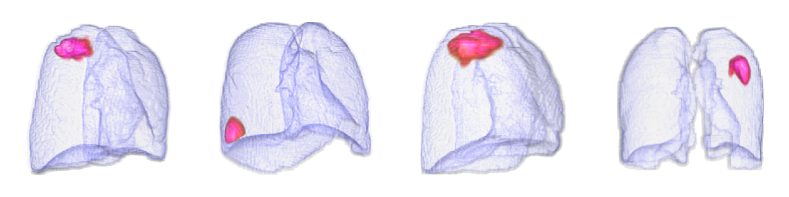

By using the internal clinical dataset from SMC of pneumonia and tuberculosis cases, we experimentally verified the superiority of the proposed VMPR-UAD through various comparative experiments. We also provide quantitative results and 3D abnormal (lesion) localization/visualization results of VMPR-UAD using the internal dataset for pneumonia and tuberculosis in the Supplementary Material to illustrate the superiority of anomaly localization by VMPR-UAD.

Finally, we evaluated the 3D abnormal (lesion) localization performance of the proposed VMPR-UAD. Of the 63 cancer cases in the MSD dataset with ground-truth annotations available, we excluded two cases (cases 38 and 96) of incorrect annotation or showing other diseases. We calculated whether the cancer area predicted by VMPR-UAD (binarized at a certain high-probability threshold) overlapped with the annotated cancer area. As a result, 57 of the 61 cases showed overlapping, demonstrating that VMPR-UAD can localize 3D lung anomalies (cancer in this case) with an accuracy of 93. Some localization examples in 3D data are shown in Fig. L. The red points in Fig. L(b) show the 3D cancer locations that the proposed method estimates with the highest confidence (i.e., location of highest pixel value in the 3D anomaly map). The red points in Fig. L(a) show the ground-truth cancer location. The ground truth and prediction shown in Fig. L confirm that VMPR-UAD correctly finds the lung anomaly 3D region. More detailed visualization results are available in the Supplementary Material. The prediction consistency can also be observed in 2D slices, as shown in Fig. M, where our anomaly localization map indicates correct cancer regions. Hence, the proposed VMPR-UAD can automatically localize or segment lesions without requiring any lesion information (i.e., using only CT slices from healthy subjects) for training.